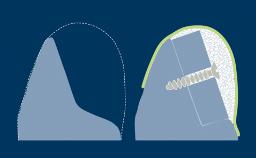

The alveolar process is composed of two types of bone: the alveolar bone proper (known histologically as bundle bone) and the supporting bone.

The bundle bone comprises the inner portion of the alveolar socket while the remaining part of the alveolar process consists of supporting bone.

The bundle bone is a periodontal tissue similar to cementum that connects the periodontal ligament to the alveolar bone.

When a tooth is removed, the developmental unit is altered, and the alveolar process resorbs.